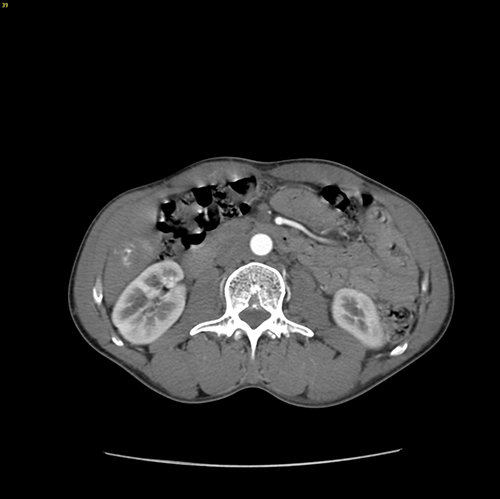

S6肝癌--腹腔镜S6部分切除